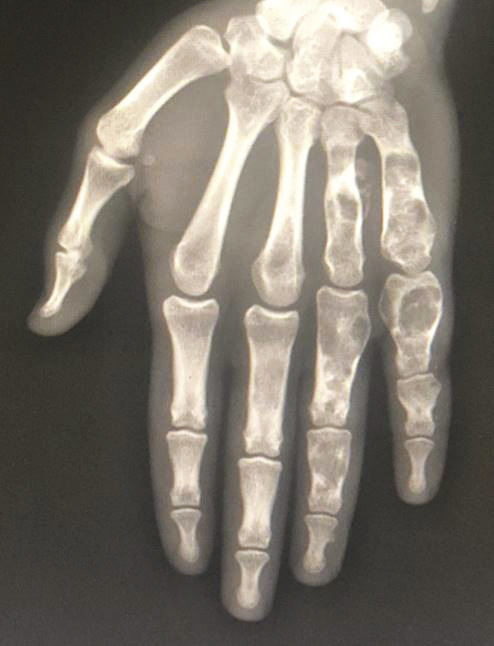

La radiographie standard met en évidence de multiples lésions osseuses lytiques métaphyso-diaphysaires géographiques, avec une fine ostéosclérose périphérique de type Ia de Lodwick, au niveau des métacarpes et des phalanges des 4e et 5e rayons de la main gauche. Ces lésions osseuses sont soufflantes, avec un discret amincissement des corticales (fig. 2 ). Une tomodensitométrie confirme les données de l’imagerie standard et ne montre pas de signes de transformation sarcomateuse (fig. 3 ). Les constatations cliniques et radiologiques permettent de poser le diagnostic de maladie d’Ollier.

La radiographie standard met en évidence de multiples lésions osseuses lytiques métaphyso-diaphysaires géographiques, avec une fine ostéosclérose périphérique de type Ia de Lodwick, au niveau des métacarpes et des phalanges des 4e et 5e rayons de la main gauche. Ces lésions osseuses sont soufflantes, avec un discret amincissement des corticales (